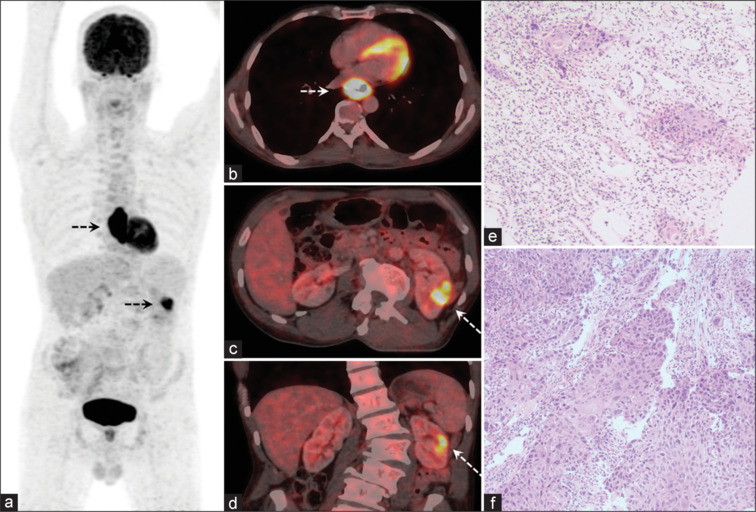

Solitary Renal Metastasis in Esophageal Squamous Cell Cancer Detected on F-18 FDG PET/CT - A Rare Presentation.

Positron emission tomography with computed tomography using fluorine-18 fluoro-D-glucose positron emission tomography-computed tomography (F-18 FDG PET/CT) is routinely used for baseline staging and response assessment for esophageal squamous cell cancer (E-SCC). Metastases in E-SCC are usually seen in regional lymph nodes and lungs with solitary metastases to the kidney being extremely rare. We present a case of solitary unilateral renal metastasis detected on baseline F-18 FDG PET/CT in an otherwise operable E-SCC.